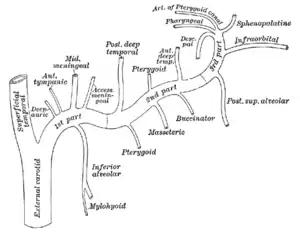

L'artère maxillaire ou l'artère maxillaire interne en ancienne nomenclature[1] (Arteria maxillaris ou Arteria maxillaris interna en latin) est une des deux branches terminales de l'artère carotide externe. Elle participe entre autres à la vascularisation de la partie inférieure de la face, de l'oreille ainsi que de certaines structures intracrâniennes.

L'artère maxillaire est la plus importante des deux branches terminales de la carotide externe, l'artère temporale superficielle étant la plus petite. Elle naît dans la glande parotide, en arrière du col de la mandibule et se dirige vers l'avant, perpendiculairement à la carotide externe. Dans de rares cas, l'artère maxillaire provient de l'artère faciale[2].

L'artère maxillaire est classiquement divisée en trois segments : un premier segment mandibulaire, un deuxième segment ptérygoïdien et un troisième segment ptérygo-palatin[3]

Après avoir irrigué une partie de la glande parotide, l'artère maxillaire quitte la loge parotidienne par la boutonnière rétro-condylienne de Juvara, en passant entre le ligament sphéno-mandibulaire médialement et le col de la mandibule latéralement[4]. Elle entre dans la fosse infra-temporale, accompagnée par le nerf auriculo-temporal. L'artère maxillaire croise ensuite le nerf alvéolaire inférieur avant d'atteindre le muscle ptérygoïdien latéral. Elle donne à ce niveau cinq collatérales :

- L'artère auriculaire profonde est la première des collatérales. Il s'agit d'une branche ascendante qui naît souvent d'un tronc commun avec l'artère tympanique antérieure[3]. Elle vascularise l'articulation temporo-mandibulaire puis remonte et transperce l'os temporal en avant du méat acoustique externe, au niveau de la fissure tympano-squameuse[5] pour irriguer la face externe du tympan.

- L'artère tympanique antérieure est également une branche ascendante de l'artère maxillaire. Elle pénètre dans l'os temporal par la fissure pétro-tympanique et s'anastomose dans la caisse du tympan avec l'artère du canal ptérygoïdien, branche de l'artère maxillaire, l'artère stylo-mastoïdienne issue de l'artère auriculaire postérieure et l'artère carotico-tympanique provenant de la carotide interne[3]. Elle vascularise la muqueuse de l'oreille moyenne et la face interne du tympan.

- L'artère méningée moyenne est la plus importante des branches de l'artère maxillaire. Depuis son origine, elle remonte vers le foramen épineux en passant entre les deux racines du nerf auriculo-temporal. Au niveau du crâne, elle remonte le long de la face latérale puis se ramifie pour irriguer les os du crâne, et une grande partie de la dure-mère. Au cours de leur trajet, l'artère méningée et ses branches creusent des sillons sur la face endocrânienne des os[6].

- L'artère méningée accessoire (ou artère petite méningée en ancienne nomenclature[1]) est une petite branche inconstante qui naît soit à proximité de l'artère méningée moyenne, soit directement de celle-ci. Elle pénètre dans le crâne par le foramen ovale pour vasculariser la dure-mère et le ganglion trigéminal. Malgré son nom, seulement 10 % du flux sanguin de cette artère atteint les structures intracrâniennes[7]. Elle irrigue ainsi le muscle ptérygoïdien médial, le chef supérieur du muscle ptérygoïdien latéral, le muscle tenseur du voile du palais, le ganglion otique, le nerf mandibulaire et l'os sphénoïde[8].

- L'artère alvéolaire inférieure (anciennement appelée artère dentaire inférieure[1]) est une branche descendante de l'artère maxillaire. Elle se dirige vers le bas, accompagnée par le nerf alvéolaire inférieur. Juste avant de pénétrer dans le canal alvéolaire inférieur par le foramen mandibulaire elle donne une branche, l'artère mylo-hyoïdienne, qui descend à la face interne de la mandibule au niveau du sillon mylo-hyoïdien pour vasculariser le muscle du même nom. L'artère alvéolaire inférieure poursuit ensuite son trajet dans le canal alvéolaire et se divise en une branche mentonnière passant par le foramen mentonnier pour vasculariser les téguments du menton, et une branche incisive qui poursuit son trajet et s'anastomose avec l'artère contro-latérale[3]. Elle permet la vascularisation des dents inférieures via des rameaux dentaires[6].

Deuxième segment

Au niveau du deuxième segment l'artère maxillaire, qui devient assez flexueuse, est satellite du muscle ptérygoïdien latéral. Elle peut passer soit médialement, entre les deux muscles ptérygoïdiens, soit latéralement, entre le ptérygoïdien latéral et le muscle temporal[6]. La variante externe semble être un peu plus fréquente que la variante interne[9],[10]. Dans sa variante superficielle, l'artère maxillaire contourne le bord inférieur du muscle ptérygoïdien latéral pour passer à sa face externe. Elle croise le nerf buccal, issu de la division antérieur du nerf mandibulaire. Dans sa variante profonde, l'artère maxillaire longe la face médiale du muscle ptérygoïdien latéral et se trouve donc dans l'espace interptérygoïdien. Sur son trajet elle croise les nerfs alvéolaire inférieur et lingual au niveau de la réunion avec la corde du tympan[6]. Elle passe ensuite entre les deux chefs du muscle ptérygoïdien latéral pour se retrouver à sa face externe. Le deuxième segment de l'artère maxillaire donne plusieurs collatérales :

- L'artère massétérique passe par l'incisure mandibulaire de la mandibule, accompagnée par le nerf massétérique issu du nerf mandibulaire. Elle s'anastomose avec des branches de l'artère transverse de la face et vascularise le muscle masséter. Cette artère est parfois absente[11].

- Les artères ptérygoïdiennes sont présentes en nombre variable. Elles sont indispensables à la vascularisation du muscle ptérygoïdien latéral, et irriguent également en partie le muscle ptérygoïdien médial[6].

- Les artères temporales profondes antérieure et postérieure sont des branches ascendantes de l'artère maxillaire. Elles remontent accompagnées par les nerfs temporaux profonds antérieur et postérieur et passent sous le muscle temporal qu'elles irriguent. Elles s'anastomosent avec l'artère temporale moyenne issue de l'artère temporale superficielle. Des petits rameaux de l'artère antérieure s'anastomosent également avec l'artère lacrymale, branche de l'artère ophtalmique, en transperçant l'os zygomatique et la grande aile de l'os sphénoïde[3].

- L'artère buccale se dirige vers le bas et l'avant accompagnée du nerf buccal. Elle se ramifie à la face externe du muscle buccinateur qu'elle irrigue, et s'anastomose avec l'artère angulaire, branche terminale de l'artère faciale, l'artère infra-orbitaire et l'artère alvéolaire supérieure et postérieure. L'artère buccale participe à la vascularisation du corps adipeux et de la muqueuse de la joue[12].

Troisième segment

Au niveau du troisième segment, l'artère maxillaire décrit une courbe à convexité antérieure qui s'appuie sur la tubérosité maxillaire et entre dans la fosse ptérygo-palatine via la fissure ptérygo-maxillaire[13]. Elle s'engage ensuite dans le foramen sphéno-palatin et devient alors l'artère sphéno-palatine. Le segment ptérygo-palatin de l'artère maxillaire compte cinq collatérales :

- L'artère alvéolaire supérieure et postérieure ou artère alvéolaire supéro-postérieure se dirige vers le bas et l'avant, le long de la face externe de la tubérosité maxillaire. Elle donne plusieurs rameaux qui vont pénétrer dans l'os maxillaire avec le nerf alvéolaire supérieur et postérieur et vasculariser les trois molaires supérieures ainsi que la muqueuse du sinus maxillaire[6]. L'artère alvéolaire supéro-postérieure se poursuit à la surface de la tubérosité maxillaire et vient irriguer les gencives supérieures. Elle se termine en rameaux s'anastomosant avec l'artère buccale et l'artère infra-orbitaire.

- L'artère infra-orbitaire passe par la fissure orbitaire inférieure et donne une branche orbitaire qui vascularisent le sac lacrymal et les muscles droit et oblique inférieur. Puis elle s'insère dans le sillon infra-orbitaire et pénètre dans le canal du même nom avec le nerf infra-orbitaire, branche du nerf maxillaire. Elle donne alors les artères alvéolaires supérieures moyenne et antérieure qui irriguent les incisives, canines et prémolaires supérieures ainsi que la muqueuse du sinus maxillaire. Au niveau du foramen infra-orbitaire, l'artère se ramifie et s'anastomose avec les artères dorsale du nez, angulaire, alvéolaire postéro-supérieure et infra-orbitaire, se distribuant ainsi aux téguments de la région infra-orbitaire[12].

- L'artère du canal ptérygoïdien ou artère vidienne est une branche très fine dirigée vers l'arrière. Elle pénètre dans le canal ptérygoïdien et traverse l'os sphénoïde accompagnée par le nerf du canal ptérygoïdien. Elle irrigue la muqueuse de la partie supérieure du pharynx, la trompe auditive et donne des rameaux s'anastomosant avec les artères tympaniques qui vascularisent la caisse du tympan[12].

- L'artère pharyngienne supérieure ou artère ptérygo-palatine est une fine collatérale qui passe par le canal palato-vaginal avec le rameau pharyngien du ganglion sphéno-palatin[14]. Elle vascularise la muqueuse du toit de la cavité nasal, du rhinopharynx, du sinus sphénoïdal et de la trompe auditive[12].

- L'artère palatine descendante (artère palatine supérieure dans l'ancienne nomenclature[1]) se dirige vers le bas et s'engage dans le canal palatin (ou palatin postérieur) avec les nerfs grand et petit palatins. Elle se divise alors en artères grande et petite palatines qui vont irriguer la muqueuse et les glandes du palais. L'artère grande palatine se poursuit vers l'avant en longeant la voûte palatine et s'anastomose avec l'artère contro-latérale puis traverse le canal incisif pour rejoindre l'artère sphéno-palatine, branche terminale de l'artère maxillaire[3].

Terminaison

Après son passage par le foramen sphéno-palatin, l'artère sphéno-palatine se divise en branches nasales postéro-latérales et septales postérieures. Elles s'anastomosent avec les artères ethmoïdales antérieure et postérieure et avec des branches de l'artère faciale. Le rameau septal se poursuit vers le bas et l'avant en creusant un sillon dans l'os vomer puis traverse le canal incisif pour rejoindre l'artère grande palatine. L'artère sphéno-palatine et ses branches assurent la vascularisation des parois latérale et septale de la cavité nasale, et des sinus frontal, ethmoïdal, sphénoïdal et maxillaire[12].